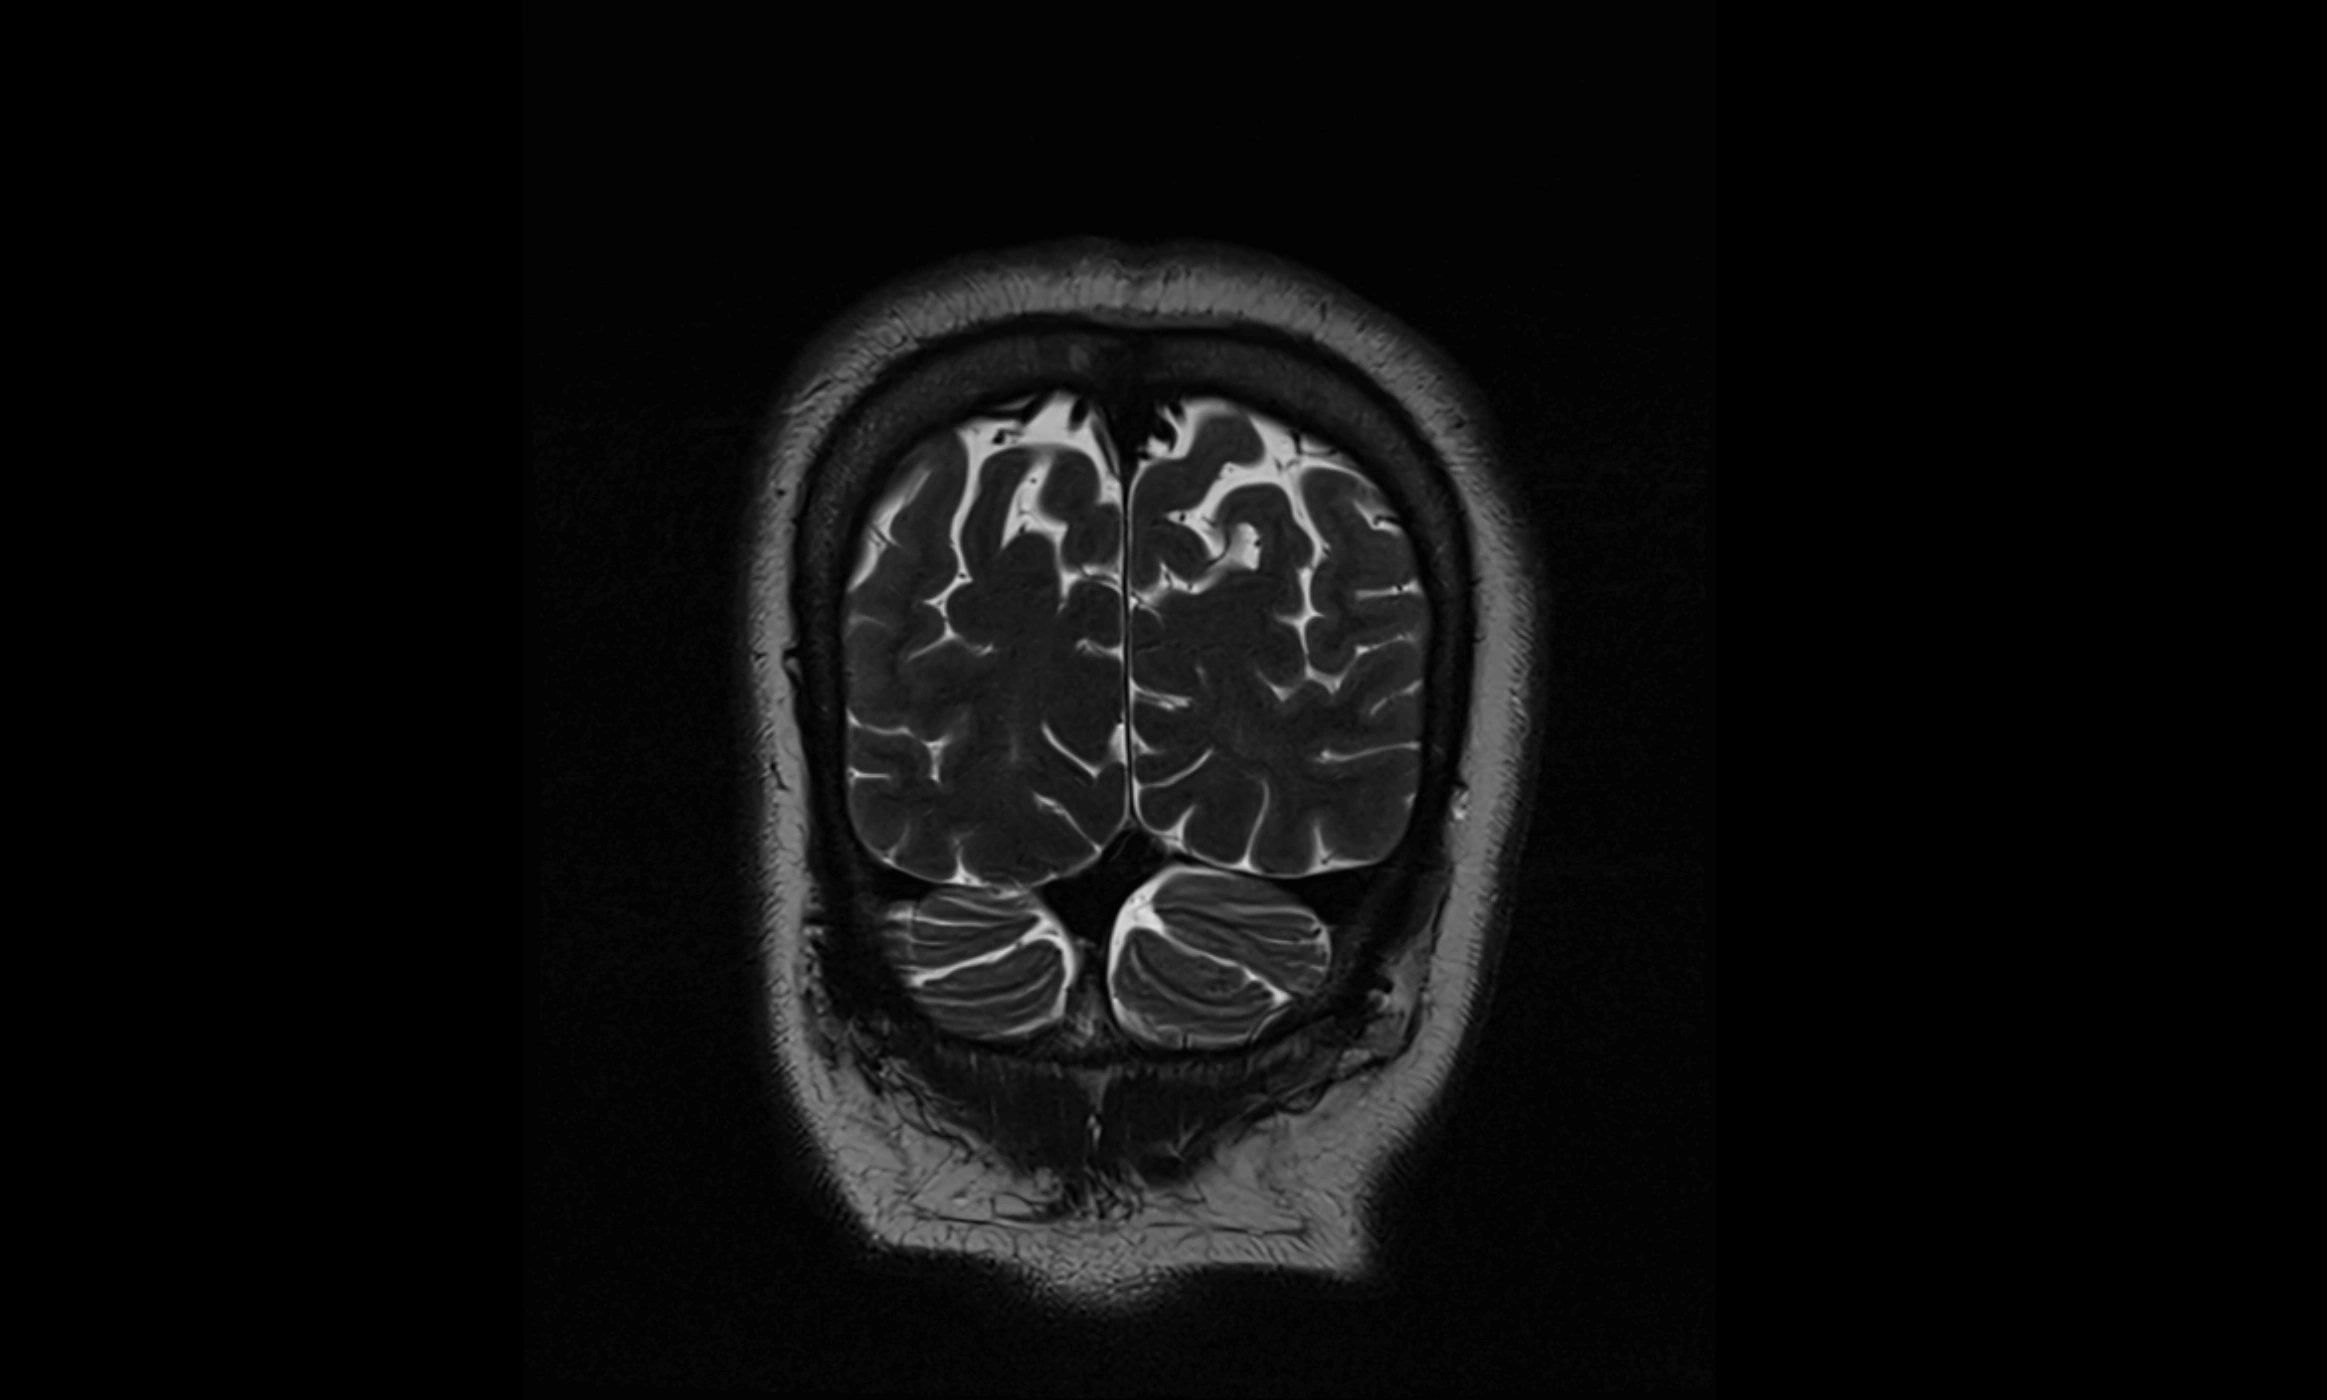

MRI images

image